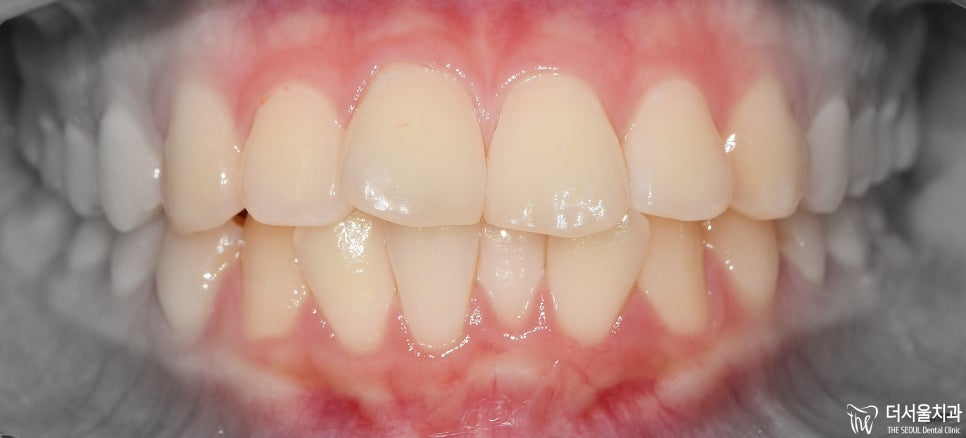

정면에서 볼 때는 앞니들의 배열 문제 이외에 돌출입 증세는 크게 느껴지지 않죠?

그리고, 안면 비대칭 또한 없는 분입니다. 이런 분들이 교정치료를 받으면 예후가 좋습니다.^^

먼저 교합면에서 보게 되면, 앞니들의 총생이 관찰됩니다.

정면에서는 뭔가…. 그렇게 고르지 않은 치열이라는게 느껴지죠?

어색한 느낌이 계속 듭니다.